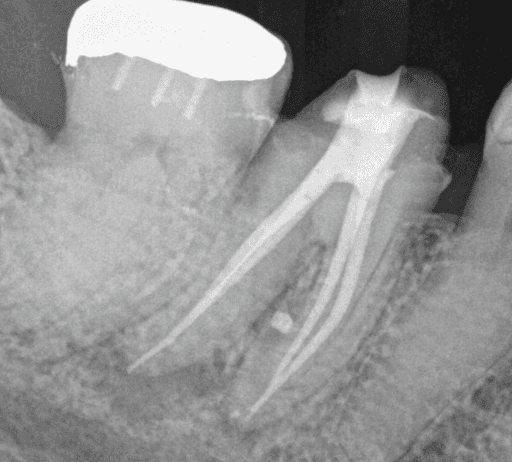

KREENA'S CASES